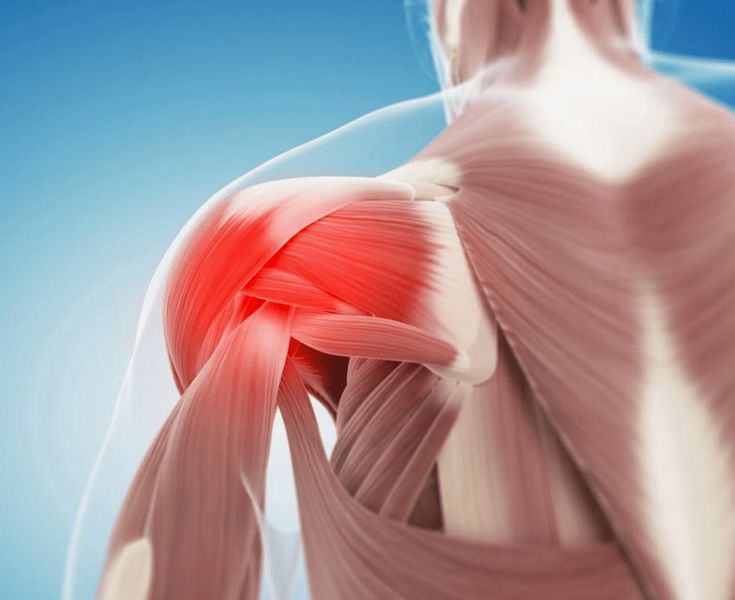

Rotator Cuff Injuries Rotator cuff tears, strains, and tendinopathies are among the leading causes of shoulder pain. These injuries often result from repetitive overhead activities, sports, or aging.

Symptoms Include:

Sharp shoulder pain

Pain while lifting or rotating the arm

Weakness in the shoulder

Night pain